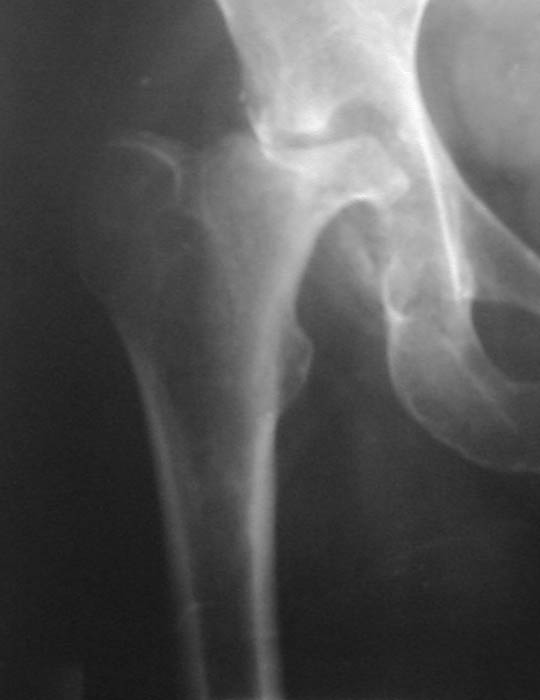

Уважаемые коллеги! Прошу Вас оказать консультативную помощь. Женщина, 44 года, инвалид 3 группы Диагноз: СКВ, асептический некроз головок обеих бедернных костей, двусторонний артроз 3-4 ст., болевой синдром, приводящая контрактура правого тазобедренного сустава,

хронический волчаночный гепатит, спленомегалия, анемия, СКВ с 2002 года (подтверждена наличием lupus-клеток), получала специфическую терапию, медрол 16 мг/сут. Боли в левом тазобедренном суставе появились в сентябре 2003 года. Динамика отражена на рентгенограммах. В марте 2004 года - синдром Мэллори-Вейса, кровотечение остановлено эндоскопически.

Ходит с тростью, хромота. Объем движений в суставах: справа - сгибание 90, разгибание 170, отведение 0, приведение 20, внутренняя ротация 15; слева - сгибание 90, разгибание 180, отведение 0, приведение 20, внутренняя ротация 0, наружная ротация 20.